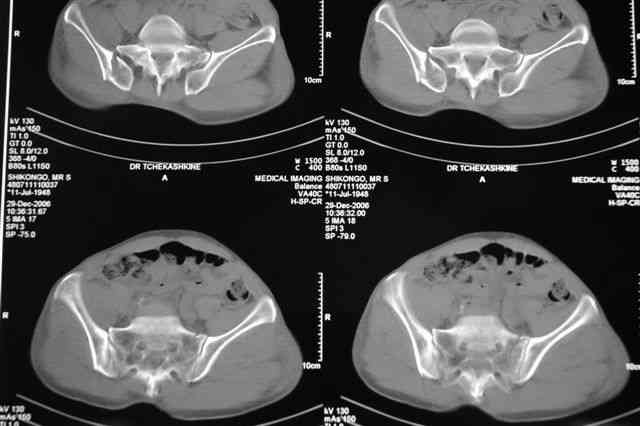

В приложении отправляю послеопер. снимки бедра и лодыжки обсуждаемого вчера больного.

В приложении послеоперационные картинки.

Чекашкин Е.И.